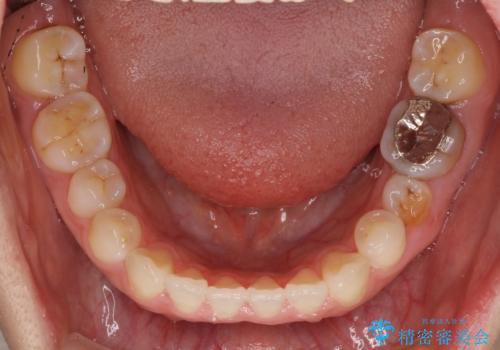

- 上下の前歯の隙間を気にして来院された患者様です。

インビザラインを用い、上下歯列のスペースを閉じていくこととしました。

治療期間中は奥歯がほとんど咬めない状態が続き、食事に大変苦労されました。

最終的には隙間もしっかりと閉じ、奥歯も咬みやすい状態でしあげることができました。